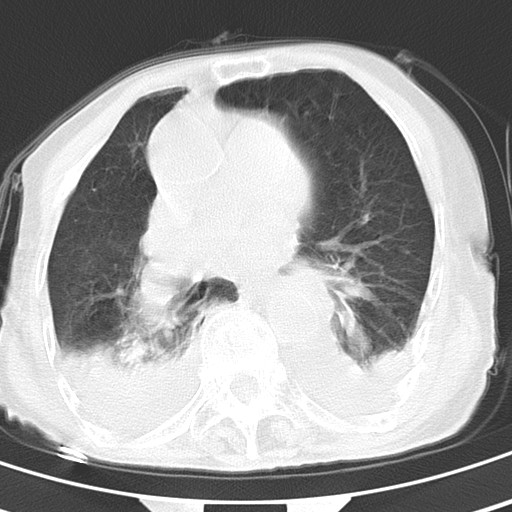

标题: CT21467:女,93岁,摔伤后检查。

女,93岁,摔伤后检查。

右肺炎症,心功能不全伴双侧胸腔积液,右下肺膨胀不全,食管裂孔疝,冠脉钙化,心包少量积液,左侧肋骨骨折,请上传骨窗.

创伤性湿肺,双侧胸腔积液。可能有食管裂孔疝,进一步检查。骨折有无根据自己的机器及片子再仔细看吧。

右侧锁骨\\肩胛骨骨折、右侧湿肺,心功能不全伴双侧胸腔积液,右下肺膨胀不全,左膈破裂或食管裂孔疝,冠脉钙化,心包少量积液,请上传骨窗.